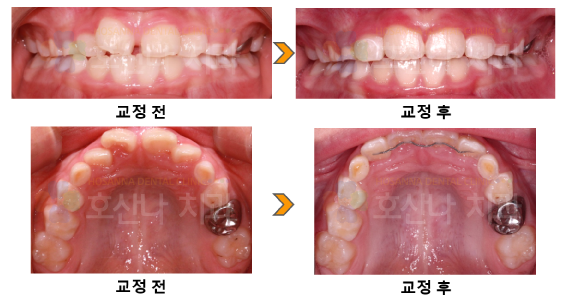

< 소아교정 >

1. 치료대상

8y 9m

2. 환자분 c.c

앞니가 비뚤어요

3. Dr.Koo Memo

상악전치의 크라우딩으로 인해 하악전치와 대합되면 치아에 외상이 가해지면서 치근흡수나 치은퇴축이 발생할 수 있습니다.

해당 아이도 치근이 짧고 치은퇴축이 있어 영구치열 완성 전이지만 앞니부위만 빠르게 개선을 해주었습니다.

교정 후  기능적,심미적으로 개선된 모습입니다.

4. 교정기간

2m